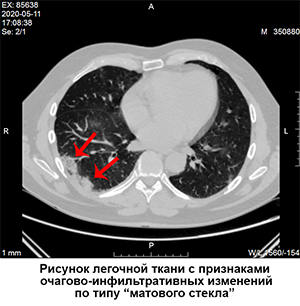

Кт лёгких

По результатам Кт у него двухсторонняя пневмония, со снижением воздушности по типу "матового стекла" субплеврально , занимая 30-35% обоих лекгих , что соответствует КТ 2 степени.